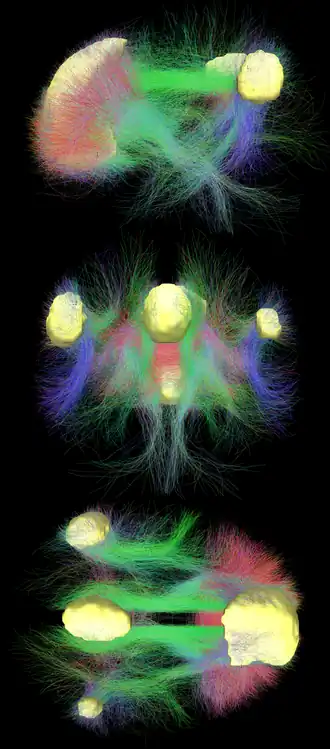

- Graphik der Verbindungen: Strukturelle Verbindungen, die das DMN unterstützen. a entspricht den Assoziationsbahnen, die die kortikalen Regionen des DMN verbinden. b veranschaulicht die Projektionsbahnen, die die Verbindungen zwischen subkortikalen und kortikalen Regionen des DMN vermitteln, aus media.springernature.com [16], Alves, P.N., Foulon, C., Karolis, V. et al. An improved neuroanatomical model of the default-mode network reconciles previous neuroimaging and neuropathological findings. Commun Biol 2, 370 (2019). https://doi.org/10.1038/s42003-019-0611-3, auf www.nature.com [17]